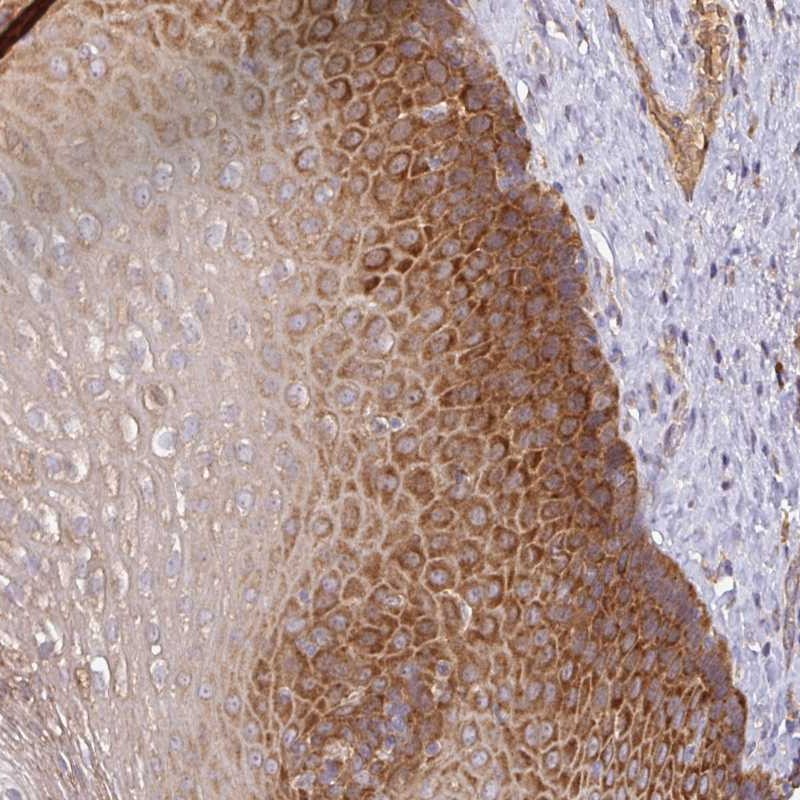

Immunohistochemical staining of human esophagus shows strong cytoplasmic positivity in squamous epithelial cells.